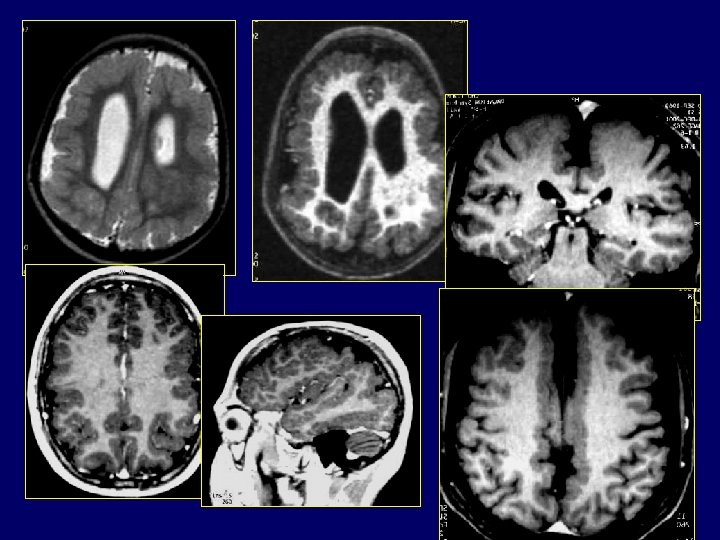

Malformations fosse postérieure complexe Dandy Walker • Hémisphères cérébelleux incomplètement formés >>>Vermis partiellement agénésique • Toile choroïdienne non perforée >> Hydrocéphalie sus jacente >>>>Malformation Dandy Walker • Toile choroïdienne perforée >>Absence d’hydrocéphalie >>>>Malformation Dandy Walker variant • Toile choroïdienne mal ouverte + cervelet normal >>Poche sus et rétro-cérébelleux: Poche de Blake

Malformations fosse postérieure complexe Dandy Walker Malformations kystiques : historiquement les plus connues ne résument pas la pathologie malformative Malformation de DW : • Élargissement de la fosse postérieure • Déplacement vers le haut des sinus latéraux, de la tente et du torcular • Dilatation kystique du V 4 • Hypoplasie ou agénésie vermienne +/compléte Diagnostic prénatal facile +++ explique la de la fréquence • L'IRM permet d'authentifier ce reliquat vermien, d'apprécier sa rotation sous la poussée du V 4 dilaté, d'étudier le retentissement de cette dilatation sur le tronc cérébral et la perméabilité de l'aqueduc de Sylvius

• DW variant : – Agénésie partielle ou hypoplasie – Dilatation kystique du V 4 – Absence d’élargissement de la fosse postérieure – Élément important +++. Nature des malformations cérébelleuses et des anomalies sus tentorielles associées. • Méga grande citerne : – Fosse postérieure élargie, liquidienne – Normalité du vermis / HC / pont – Diagnostic différentiel : KA rétro ou sous cérébelleux mais peu d’implications pronostiques ou pratiques

MALFORMATIONS DE LA FOSSE POSTERIEURE • Agénésie vermienne partielle sans poche liquidienne Signes caractéristiques en IRM : • Lobe postérieur absent • Lobe antérieur petit et dysplasique • Fissures vermiennes mal identifiables • HC anormalement accolées en frontal • Pédoncules cérébelleux étirés « signe molaire » • V 4 déformé / absence de vermis inférieur – globuleux, bord postérieur bi concave « signe ombrelle »

• Rhombencephalo-synapsis – Malformation rare – Fusion des HC et absence de vermis – Signes associées : • Fusion noyaux dentelés, pédoncules cérébelleux, thalamus • Absence de septum pellucidum • Anomalies du système limbique • Hydrocéphalie – Diagnostic prénatal possible • Autres malformations non kystiques Dysplasies : Diffuses avec souvent atteinte sus tentorielle : Walker-Warburg ou lissencephalie type 2 Infection à CMV (tropisme du CMV pour les cellules en prolifération) Focales : Hétérotopis, dysplasie focale, anomalie de la foliation Lhermite. Duclos